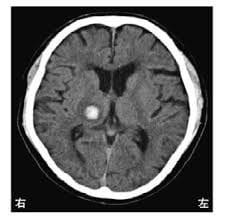

1. 頭部CT:X線を用いて脳の画像を作成し、主に急性期脳出血の有無(右図の白い病変が脳出血)を確認します。急性期の脳梗塞では変化を捉えることがしばしば困難なこともあります。撮影時間は、約5分です。

脳卒中2